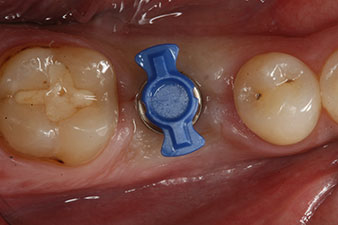

L’implant a été posé comme prévu après élimination complète du tissu de granulation (blueSky, bredent).

Le couple utilisé pour la pose guidée était de 43 Ncm.

En outre, après avoir vissé une tige de mesure (SmartPeg) spécialement conçue pour l'implant, la valeur ISQ a été mesurée à l’aide de la sonde du module W&H Osstell ISQ.

Ce module est fourni en option avec l’Implantmed de W&H et est fixé au moteur d’implantologie (cf. Fig. 11). La valeur ISQ adimensionnelle mesurée immédiatement après l’insertion était de 64 dans l’axe oro-vestibulaire et de 68 dans l’axe mésio-distal (valeur maximale = 100).

Ces valeurs auraient pu indiquer une cicatrisation ouverte, voire une restauration immédiate. Étant donné le volume osseux crestal insuffisant au niveau de l’implant, une augmentation osseuse a été pratiquée localement à l’aide des fragments osseux recueillis lors de la préparation du lit implantaire, et des points de suture effectués pour éviter le contact de la salive.